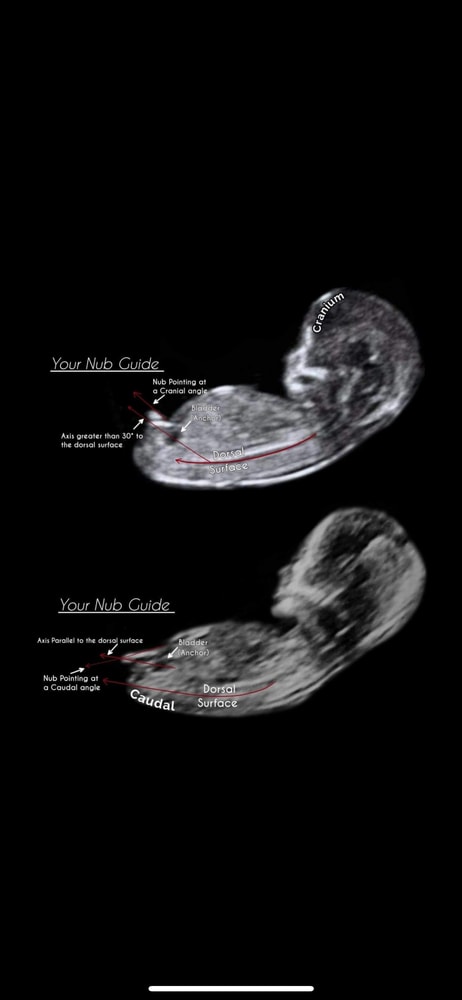

На этом фото можно увидеть различия! Сверху Мальчик. Снизу Девочка.